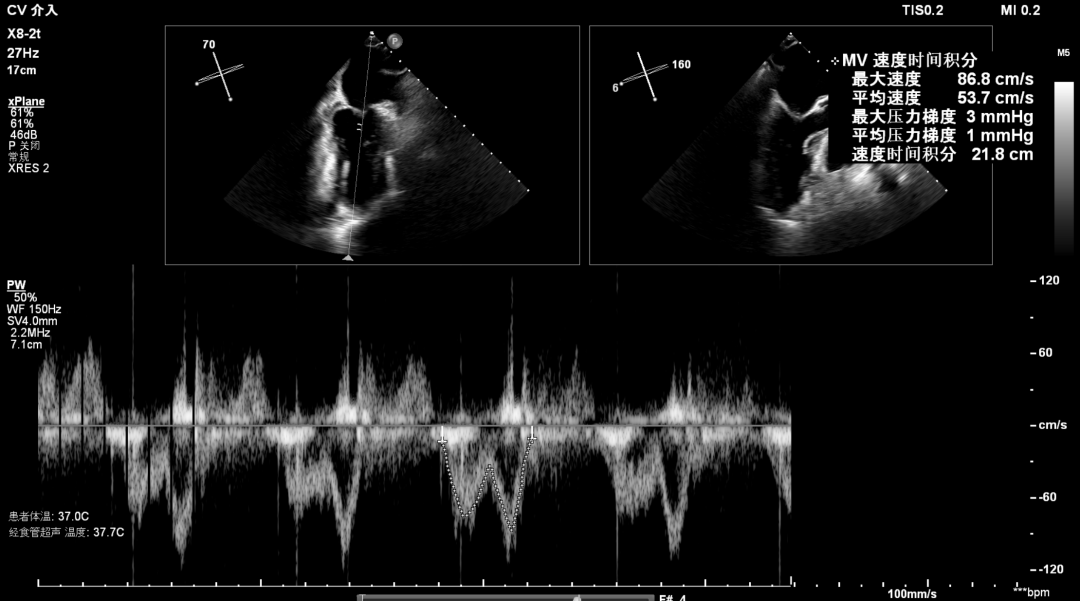

术后超声

最终在A3P2位置夹合,前叶夹合量10mm,后叶夹合量8mm,剩余瓣口面积3.45cm²,平均跨瓣压差2mmHg,反流基本消除。